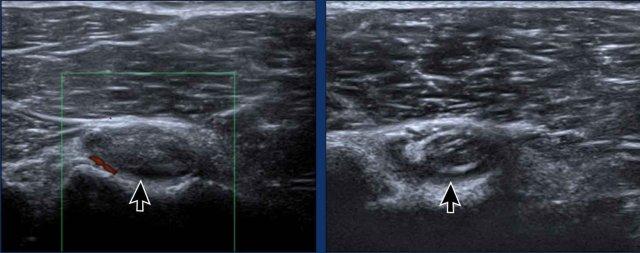

Viêm khớp cùng đòn

Hình ảnh này của một nam vận động viên 19 tuổi bị chấn thương trong một trận đấu vật.

Không có dấu hiệu viêm khớp nhiễm khuẩn và anh được chẩn đoán viêm khớp sau chấn thương.

Tình trạng của anh cải thiện với thuốc kháng viêm và nghỉ ngơi.